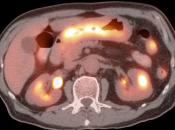

The difficulty with PET/CT imaging and gastric cancer is that it is both easy to overlook and easy to over-call.

Normal FDG uptake involving the stomach can be extremely variable. It is not uncommon to see diffuse intense uptake throughout the entire stomach or intense uptake limited to only a segment of the stomach (fundus, body or antrum).

In general, we raise a suspicion of gastric malignancy if:

• Focal or regional hypermetabolic activity is accompanied by at least the suggestion of associated wall thickening (often difficult to assess if the patient’s stomach is suboptimally distended with water or oral contrast);

• Uptake is extremely focal (more likely to represent malignancy or ulcer);

• Focal/segmental uptake is extremely intense.